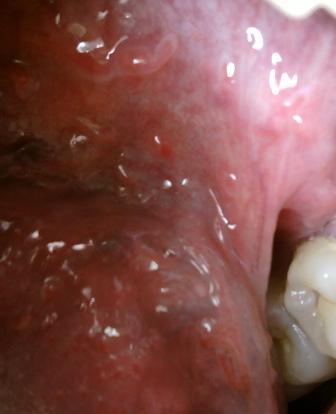

尖锐湿疣的危害您了解多少?尖锐湿疣发病绝大多数患者是通过不洁净的性关系而发病的。所以建议大家在平时的时候一定奥接身自爱,不要随便和别人发生性关系。以免不小心感染病毒而得病。随着时间的退役,湿疣体就会逐渐增大,患者在承受痛苦的同时,也会给日后的治疗带来很大的难度。会诱发炎症,影响生育,导致癌变。研究和统计表明,性生活的年龄也是ca的危险因素、免疫功能。资料表明,免疫力低下的人患病率是比较高的。吸烟,研究表明,吸烟者ca的发病率比不吸烟者高3倍多,饮酒,因为饮酒影响了机体t淋巴细胞的活性,抑制了机体的免疫力。避孕措施,任何疾病早发现早治疗,对病情的康复才越有利,不管是采用何种治疗方法,适合自己的病情才是最好的,而且治疗效果也是最明显的。